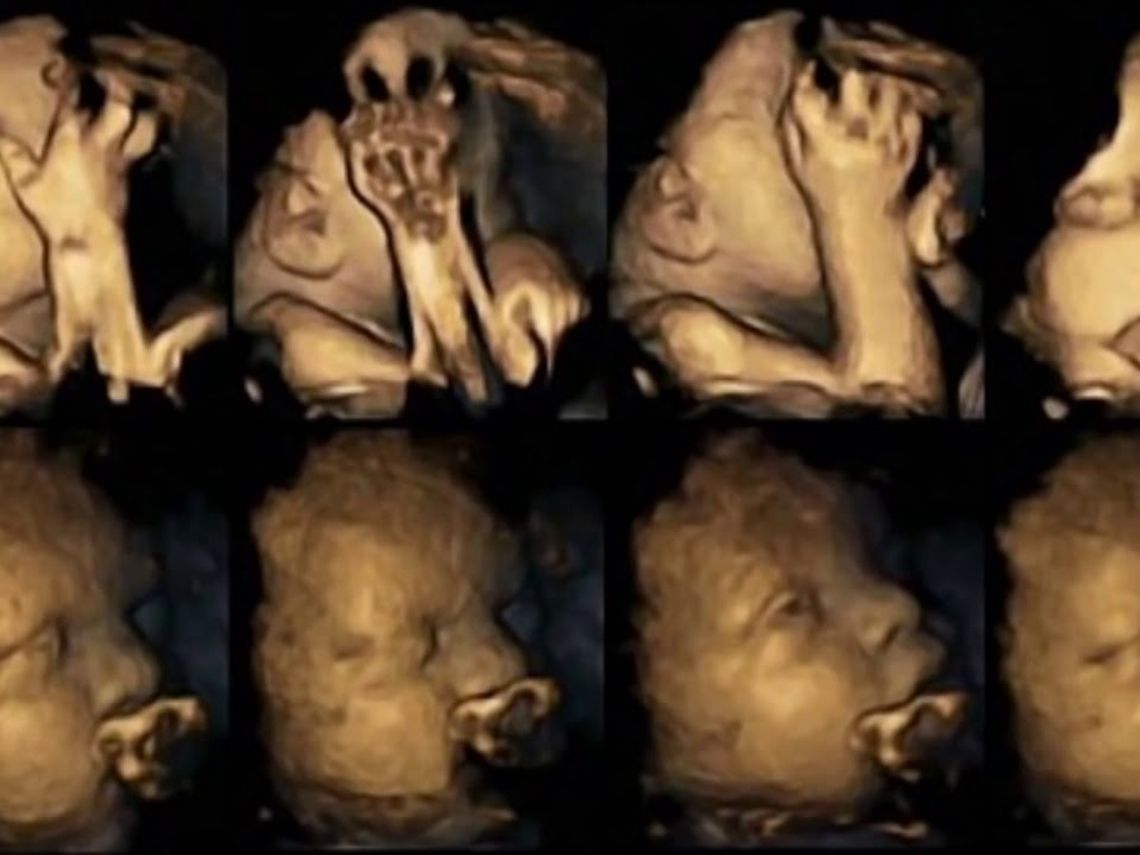

¿Cómo influye una embarazada que fuma en los gestos de su bebé? Científicos de la Universidad de Durham muestran en un ecografía 4D la razón definitiva que podría ayudar a que las embarazadas dejen de fumar.

Ecografías en 4D nos muestran los efectos del tabaco en los bebés aún sin nacer, según una nueva investigación de las inglesas universidades de Durham y de Lancaster. Una evidencia más de lo perjudicial que supone fumar embarazada.

Si eres fumadora habitual, y el tabaco te tienta constantemente a pesar de estar embarazada te gustará ver la carita que pone tu bebé cuando le das una calada al cigarro. Los efectos nocivos del consumo de tabaco durante el embarazo pueden reflejarse claramente en los movimientos faciales del bebé como demuestra este estudio realizado con 20 mujeres en la semana 32. Se les realizaba una ecografías en 4D y se puede observar una secuencia de movimientos distintas a las que no fuman.

El estudio se realizó en el Hospital de la Universidad James Cook en Middlesbrough, en el que cuatro de las pacientes fumaba un promedio de 14 cigarrillos al día. Después de estudiar sus exploraciones a las 24, 28, 32 y 36 semanas, se detectó que los fetos cuyas madres fumaban continuaron mostrando tasas significativamente más altas de movimiento de la boca y se tocaban la cara de manera más habitual que los niños de las pruebas realizadas a las no fumadores. Además se comprobó que los bebés de madres fumadoras disminuían los movimientos normales que se esperan de un feto durante el embarazo.

¿La razón? Los investigadores, que han publicado el estudio en la revista Acta Paediatrica,  sugirieron que esto podría ser que el sistema nervioso central fetal, que controla los movimientos en general y movimientos faciales, no se desarrolla a la misma velocidad y de la misma manera que en los fetos de las madres que no fumaron durante el embarazo.

En común con otros estudios, esta nueva investigación también ha demostrado que el estrés de la madre tienen un impacto significativo en los movimientos fetales, pero que el aumento de los movimientos de la boca y el tacto fue aún mayor en los bebés cuyas madres fumaron.